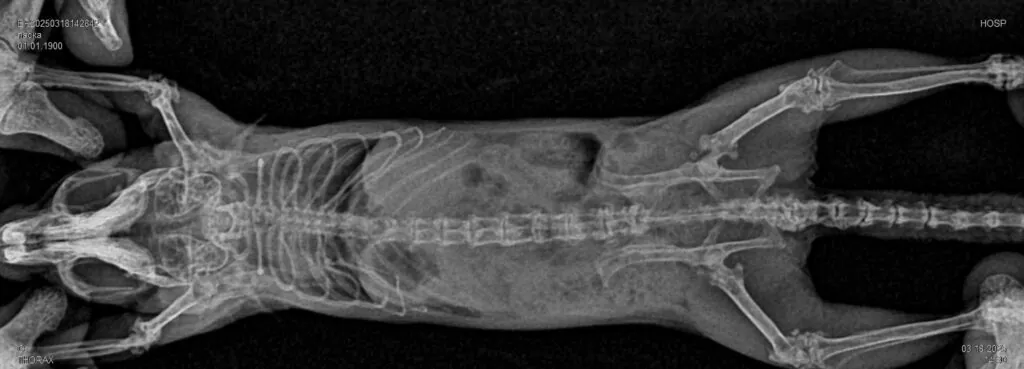

- Для исключения патологий опорно—двигательного аппарата: переломов, дегенеративных изменений костной и хрящевой ткани, дисплазии тазобедренного и локтевого суставов, новообразований костей и ряда других патологий.

Возрастные животные особенно часто подвергаются риску развития патологии, при которой происходит разрушение суставного хряща, рентгенография помогает определить явные изменения в суставах, такие как: износ хряща, образование костных наростов -остеофитов.

- При исследовании позвоночника — с помощью рентгенографии особенно в случае появления у животного неврологических симптомов, хромоты, болей в области спины и двигательных расстройств определяют патологические изменения костной системы и их источники: дегенеративные заболевания позвоночника, такие какие спондилез или артроз; деформации позвоночника.